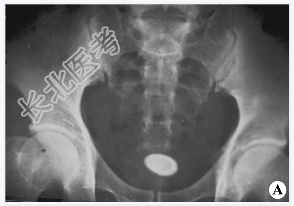

- [材料题] 男性,55岁。因反复尿频.尿急.尿痛伴肉眼血尿5年入院。查体:心、肺(-),腹平软,下腹部压痛。行腹部平片检查。

- 简答题1、请问该病诊断是什么?

- 简答题2、膀胱结石的主要症状是什么?

- 简答题3、如何诊断膀胱结石?

- 简答题4、膀胱结石的治疗方法有哪些?